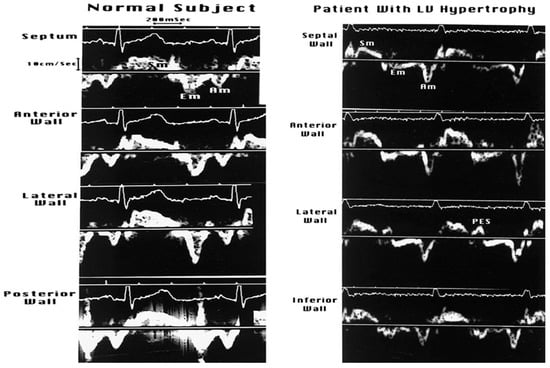

3.2.3. Doppler Tissue Imaging (DTI)

- Gorcsan, J., 3rd. Tissue Doppler echocardiography. Curr. Opin. Cardiol. 2000, 15, 323–329. [Google Scholar] [CrossRef] [PubMed]